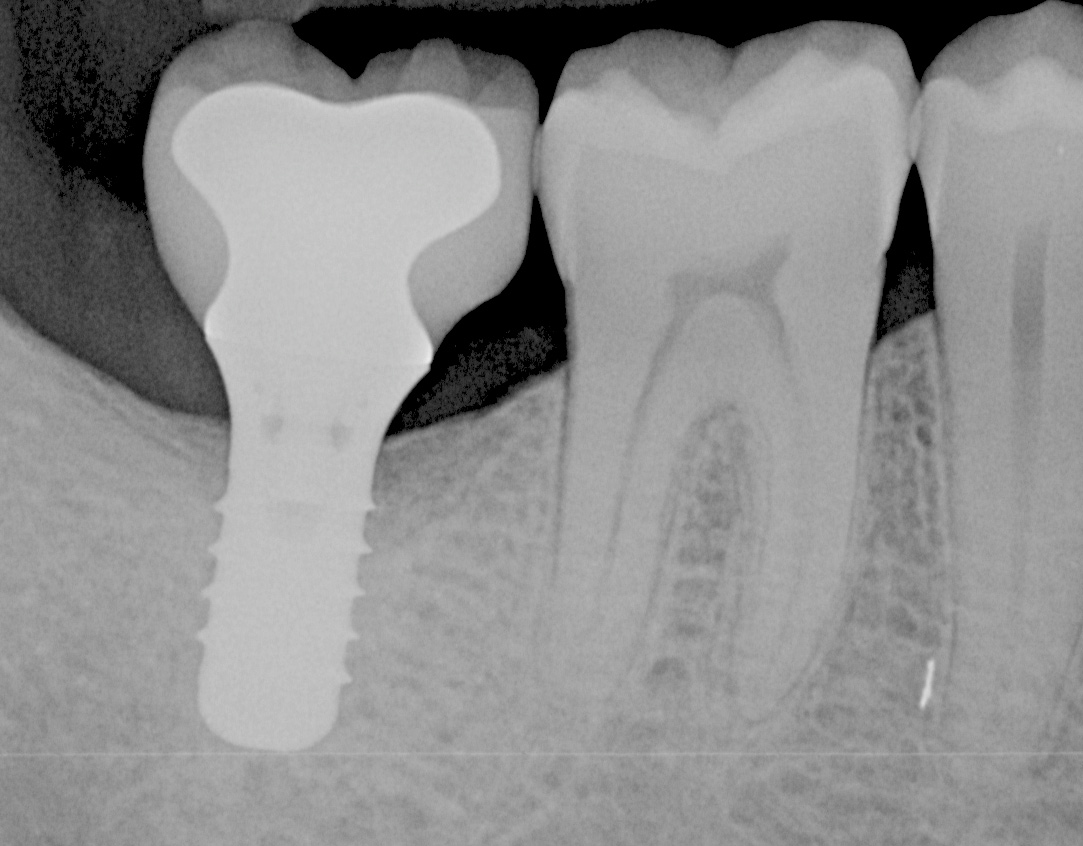

Fig 5. Radiograph of a mandibular right first molar implant in a 31-year-old woman taken 1 year after placement. No bone loss beyond physiologic remodeling has occurred; there is a suggestion of possible cement at the distal.

Figure 5